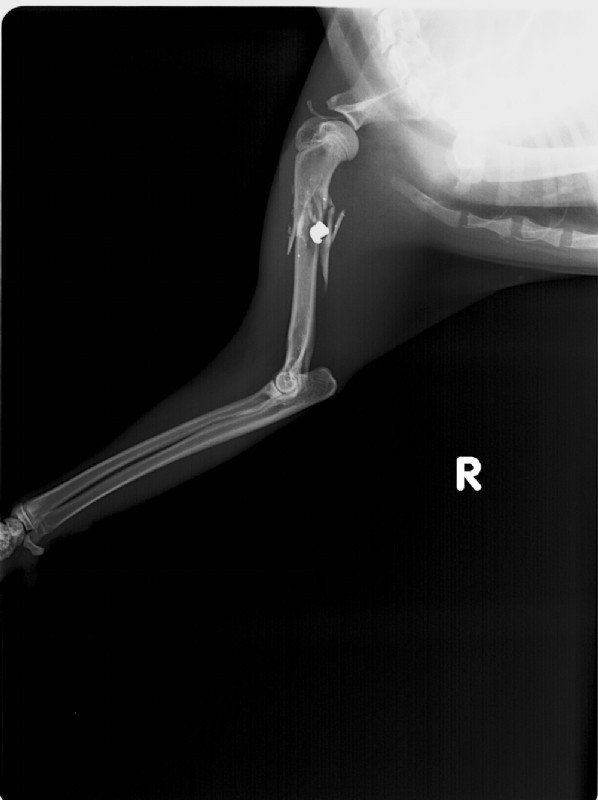

Gründe für plötzlich auftretende oder immer wiederkehrende Lahmheiten sind vielfältig. Eine genaue allgemeine und orthopädische Untersuchung sowie Röntgenaufnahmen bringen meist Klarheit in die Ursache der Erkrankung.

• Diagnostik und Behandlung plötzlich auftretender oder immer wiederkehrender Lahmheiten

• orthopädische Operationen